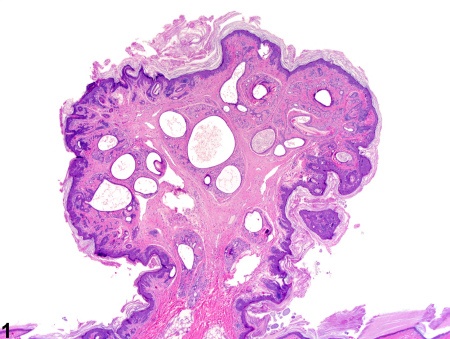

هامارتوما یک تومور غیرسرطانی (خوشخیم) است که از همان سلولهای موجود در بافت اطراف ساخته شده است، اما این سلولها و بافتها به صورت نامنظم و بینظم تومور میکنند. بیشتر هامارتوماها هیچ علامتی ایجاد نمیکنند و جدی نیستند. اگر هامارتوما مشکلی ایجاد کند، معمولاً با جراحی برطرف میشود.

هامارتوما (تلفظ: هَم-آر-تُو-ما) یک تومور شبهتوموری است که میتواند در هر جای بدن ظاهر شود. وقتی مردم کلمه «تومور» را میشنوند، اغلب به سرطان فکر میکنند، اما هامارتوماها سرطان نیستند. آنها فقط ترکیبی از همان سلولها و بافتهایی هستند که به طور طبیعی در آن ناحیه از بدن وجود دارند، اما به صورت نامنظم تومور کردهاند.

• پولیپهای هامارتوماتوز (در دستگاه گوارش)

• سندرم پوتز-جگرز (PJS): افزایش خطر هامارتوما در مثانه، روده، ریه و معده

هامارتوما: ترکیب نامنظم از بافتهای طبیعی همان ناحیه